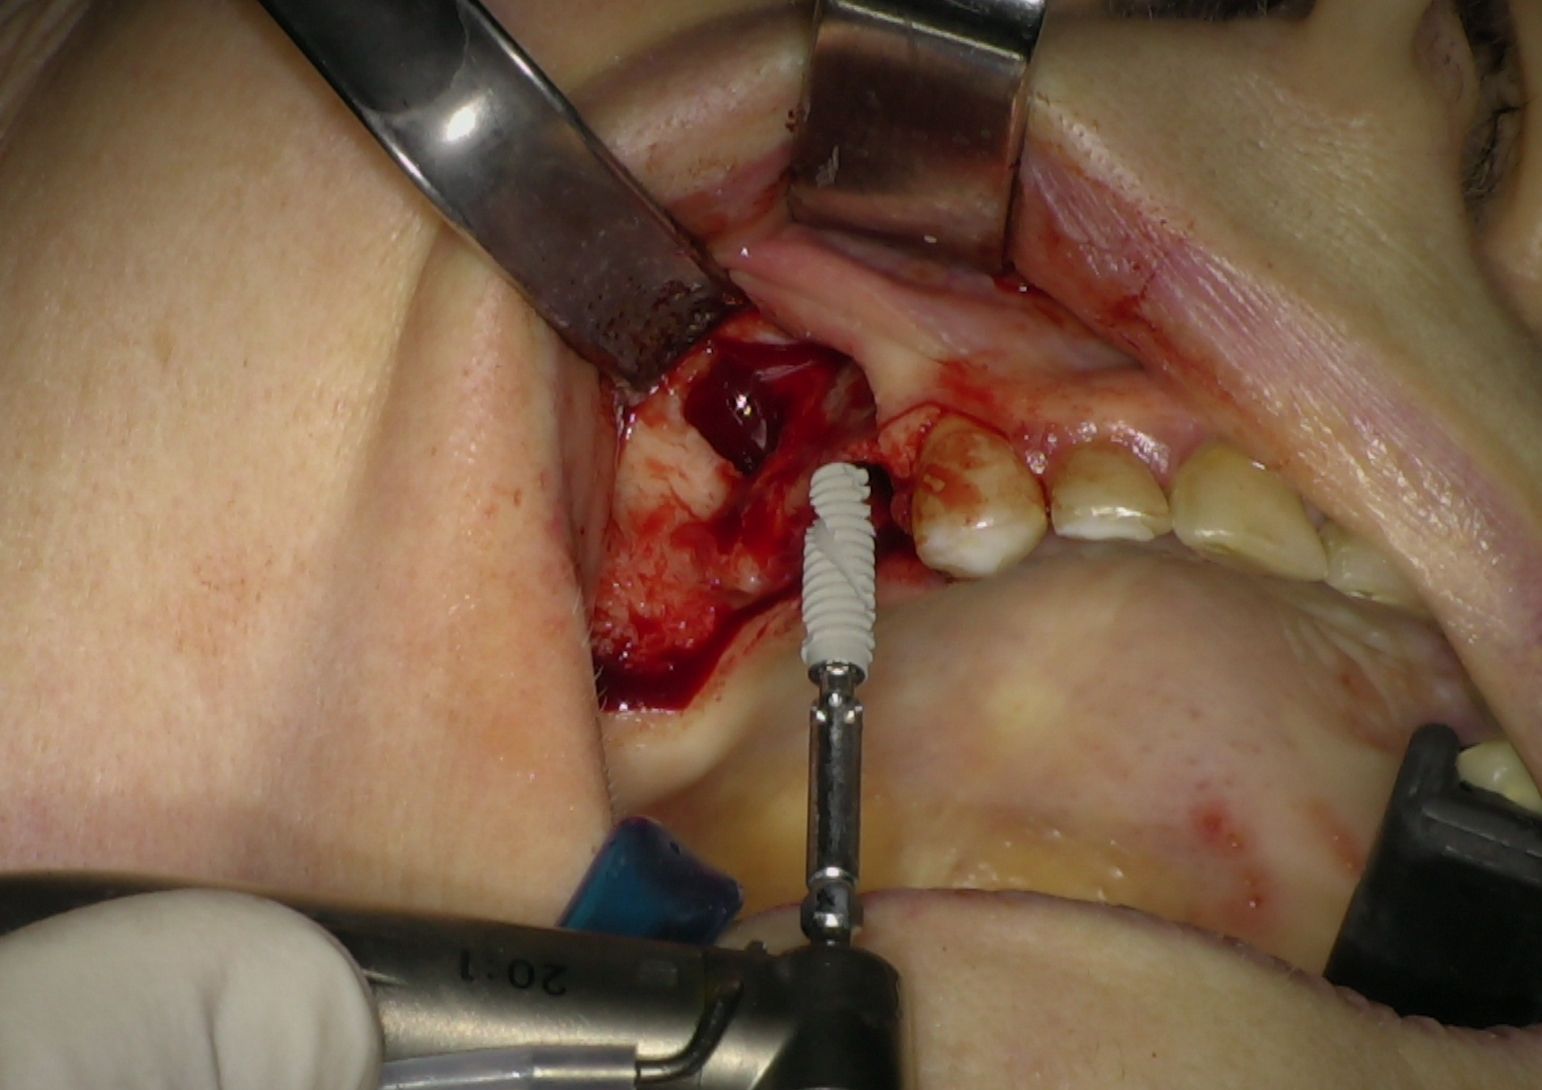

Nei settori posteriori, caratterizzati da significativa atrofia ossea e da pneumatizzazione del seno mascellare, è stato adottato un approccio transinusale. È stata pertanto realizzata una finestra laterale per consentire il sollevamento della membrana di Schneider (Fig. 3), procedura eseguita con particolare attenzione per preservarne l’integrità. Successivamente i siti implantari sono stati preparati con una traiettoria inclinata che attraversa la cavità sinusale, permettendo l'ancoraggio nell'osso basale anteriore. Sono stati quindi inseriti due impianti BT-Rhyno (Fig. 4), progettati specificatamente per l'inserimento transinusale e in grado di garantire adeguata stabilità anche in presenza di ridotto spessore osseo crestale.

Fig. 4 - Impianti BT-Rhyno